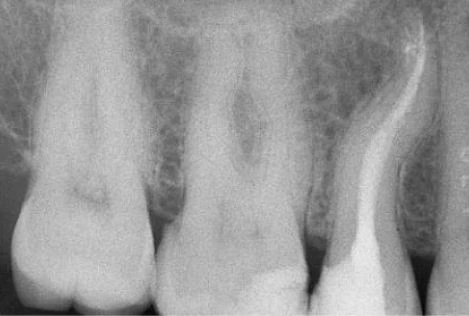

Hình 11.42. Răng nanh trên với hai ống tủy. Hai miệng ống tủy cùng nằm trong xoang tủy cho hình ảnh nòng súng đặc trưng